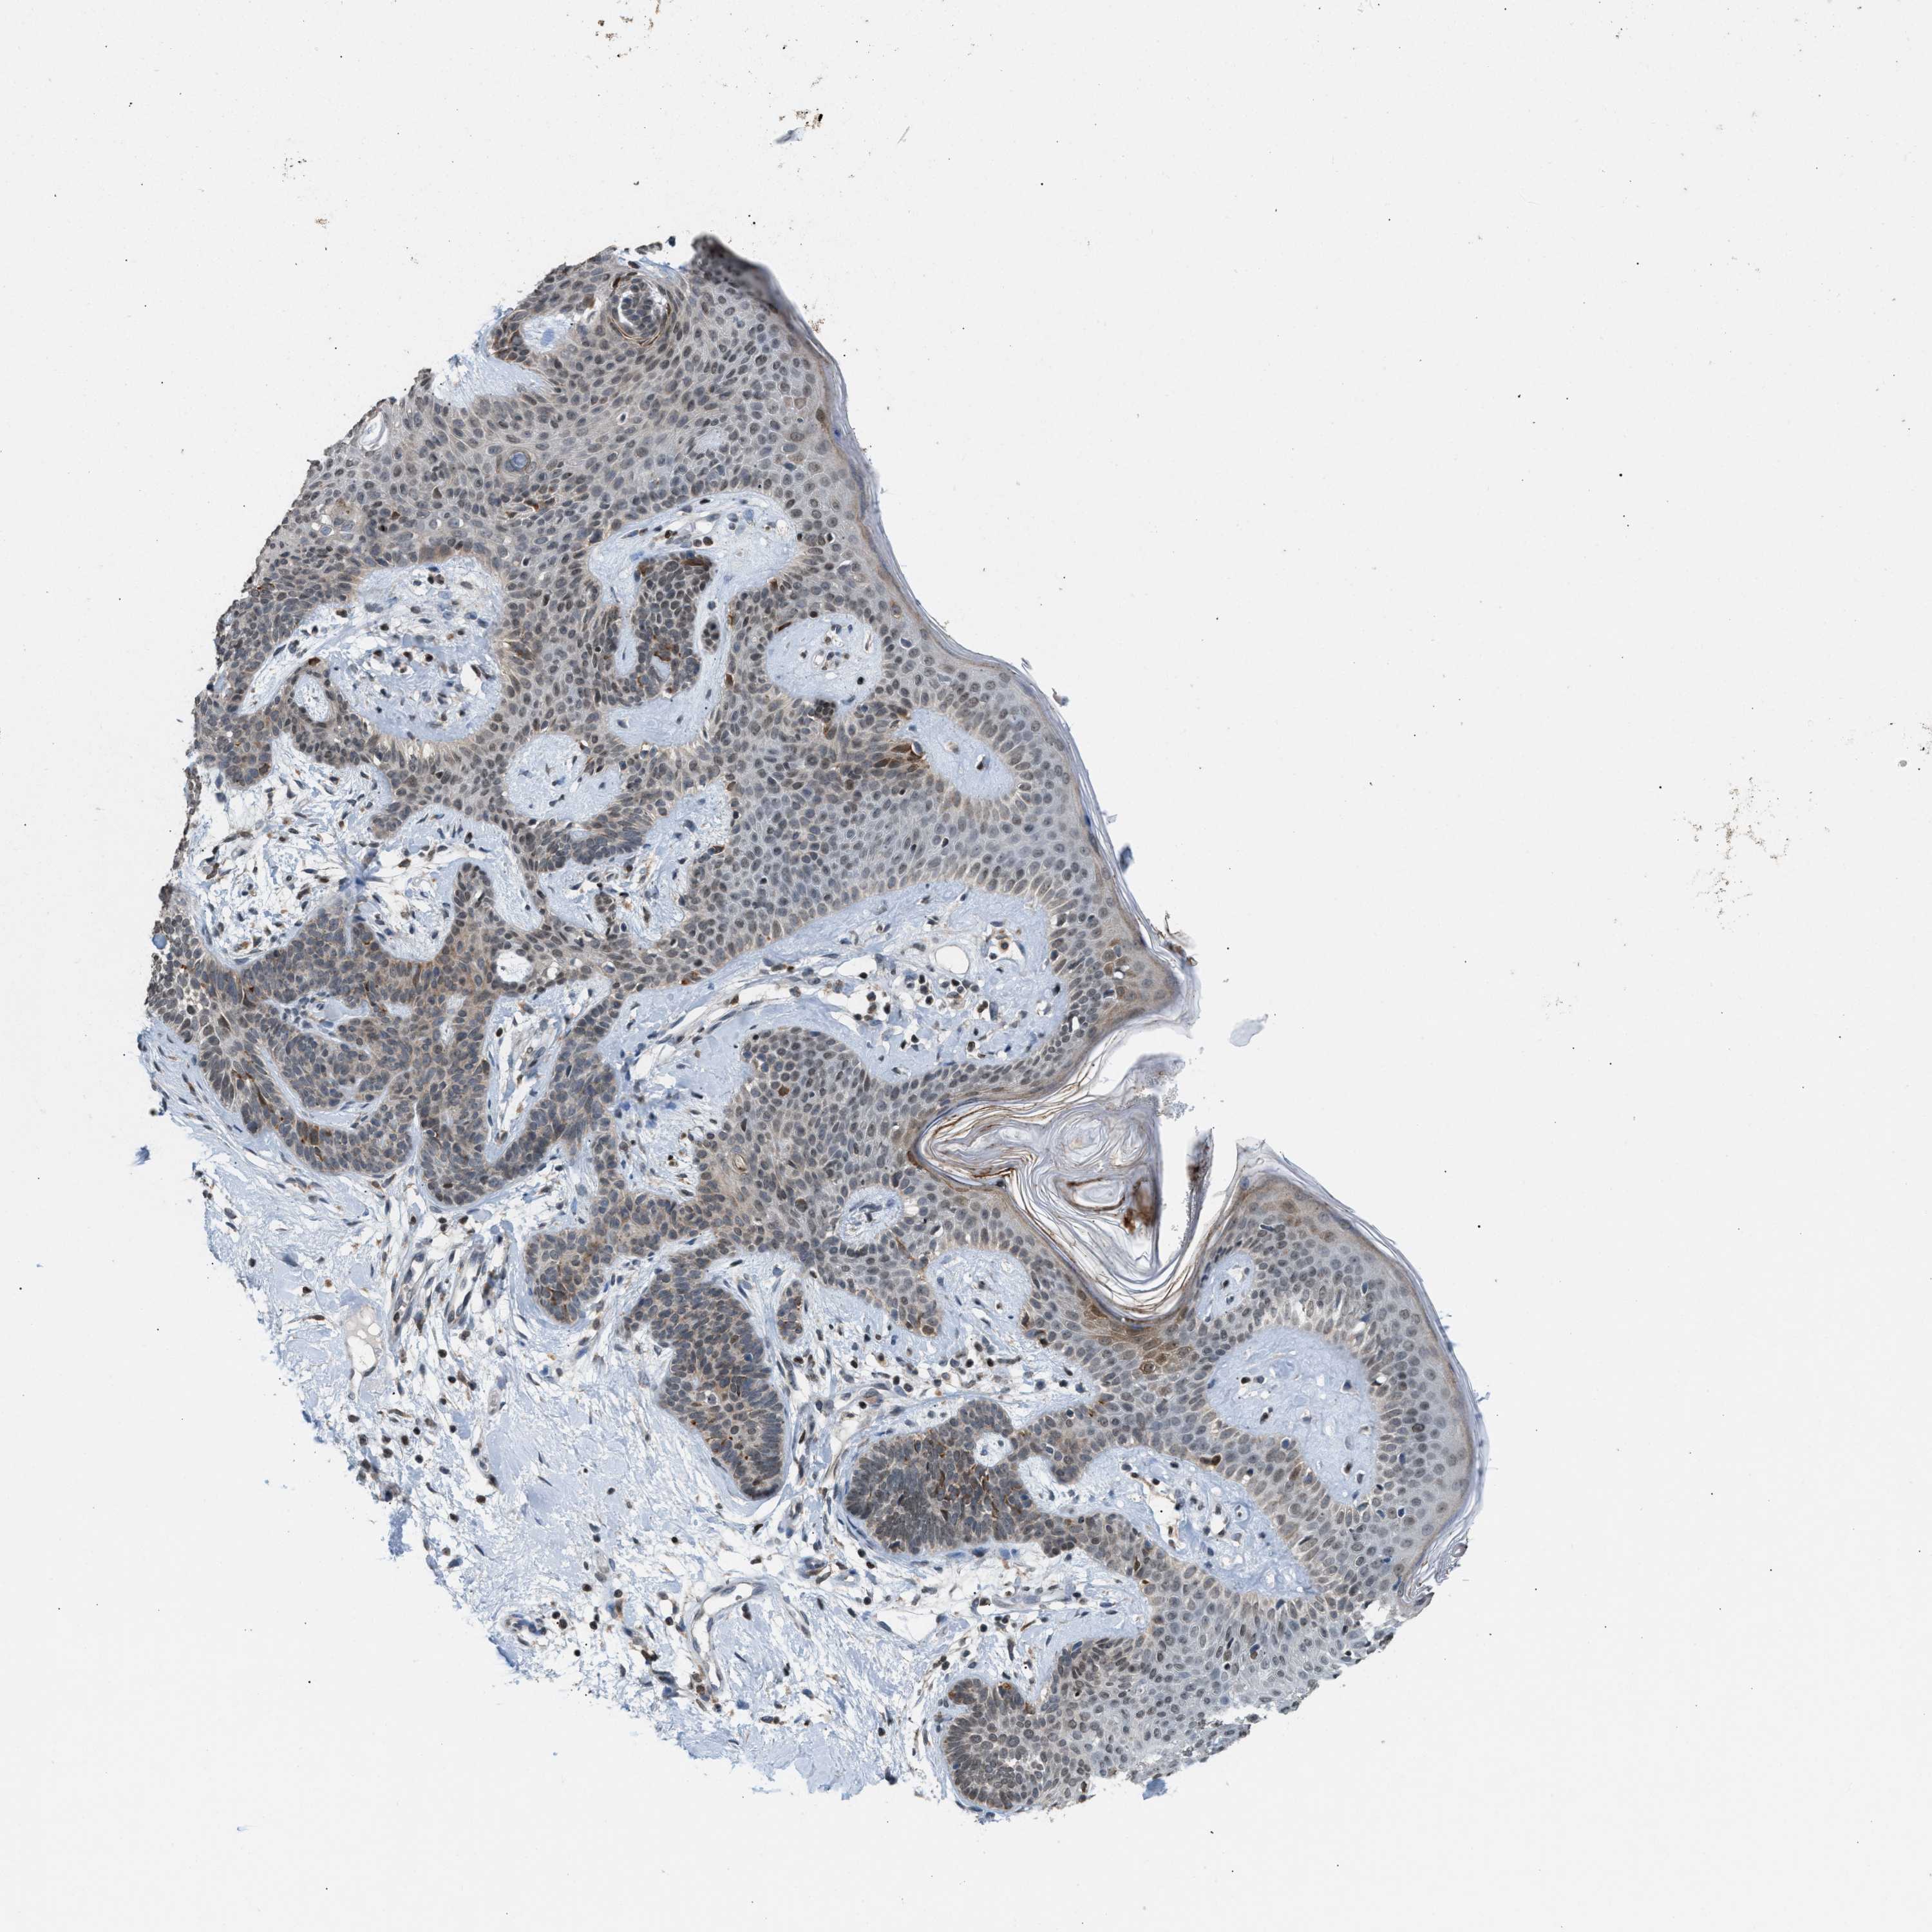

SKIN CANCER - Protein expressioni

A mouse-over function shows sample information and annotation data. Click on an image to view it in a full screen mode. Samples can be filtered based on level of antibody staining by selecting one or several of the following categories: high, medium, low and not detected. The assay and annotation is described here.

Each image is clickable and will lead to virtual microscopy that enables deeper exploration of all samples and also displays staining intensity scores, fraction scores and subcellular localization as well as patient and tissue information for each sample.

Antibody HPA022470

Staining

High

Medium

Low

Not detected

Intensity

Strong

Moderate

Weak

Negative

Quantity

>75%

75%-25%

<25%

None

Location

Nuclear

Cytoplasmic/membranous

Cytoplasmic/membranous,nuclear

Squamous cell carcinoma, NOS